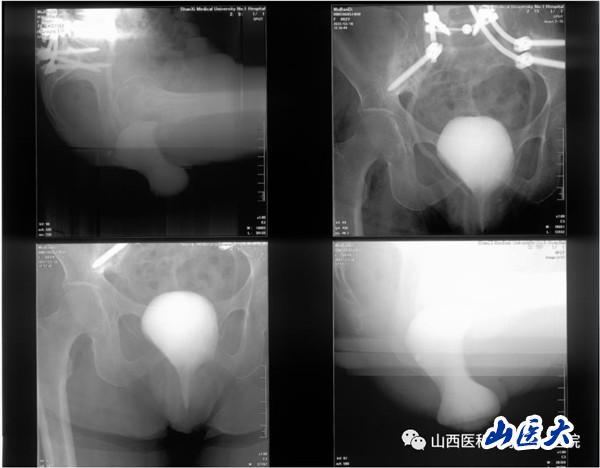

患者女性,62歲,盆腔臟器脫垂合并骶骨缺損,近年來輾轉(zhuǎn)北京及省內(nèi)各大醫(yī)院尋求外科治療,但均未能如愿。